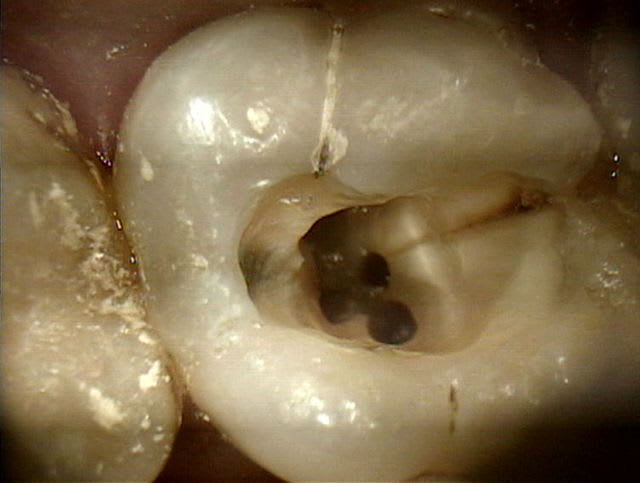

Un patient est venu en urgence pour des douleurs dentaires sur tout le côté droit, ne pouvant définir la dent en cause. A l'interrogatoire, tout a commençé il y a quelques jours avec une douleur aux cervicales, douleur qui s'est propagée aux régions dentaires sup et inf. L'examen clinique et radiologique rétoalvéolaire ne montrait apparement rien de particulier. J'ai demandé un OTP + radio des sinus. Le patient est revenu 3 jours après avec les radios qui n'ont rien montré de particulier. j'ai rééxaminé le patient, et la seule dent qui répondait à la percussion était la 16 (petit amalgame occlusal). Test de vitalité pas très net, avec réaction positive assez tardivement. J'ai enlevé l'amalgame et fraisé de plus en plus profond sans réponse pulpaire. Dès que j'ai écorné la pulpe, le patient a réagit. j'ai plaçé un pulparthrol + IRM.

Le patient est revenu hier, la douleurs s'était calmée et j'ai dévitalisée de la dent.Mais en regardant bien, j'ai remarqué un trait de fissure mésial partant de la face occlusale et se dirigeant vers l'une des entrée canalaire mésiale.

Pas de mobilité.